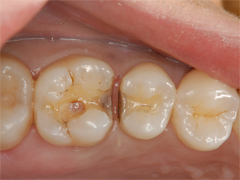

保険診療によるインレー治療がされていましたが、フロスがひっかかることと銀歯を取り替えたいとのことでセラミックスインレーでの治療を希望(当院長治療症例)

不適合な金属に汚れが溜まり、金属と歯とのすき間にむし歯の再発が起きています。